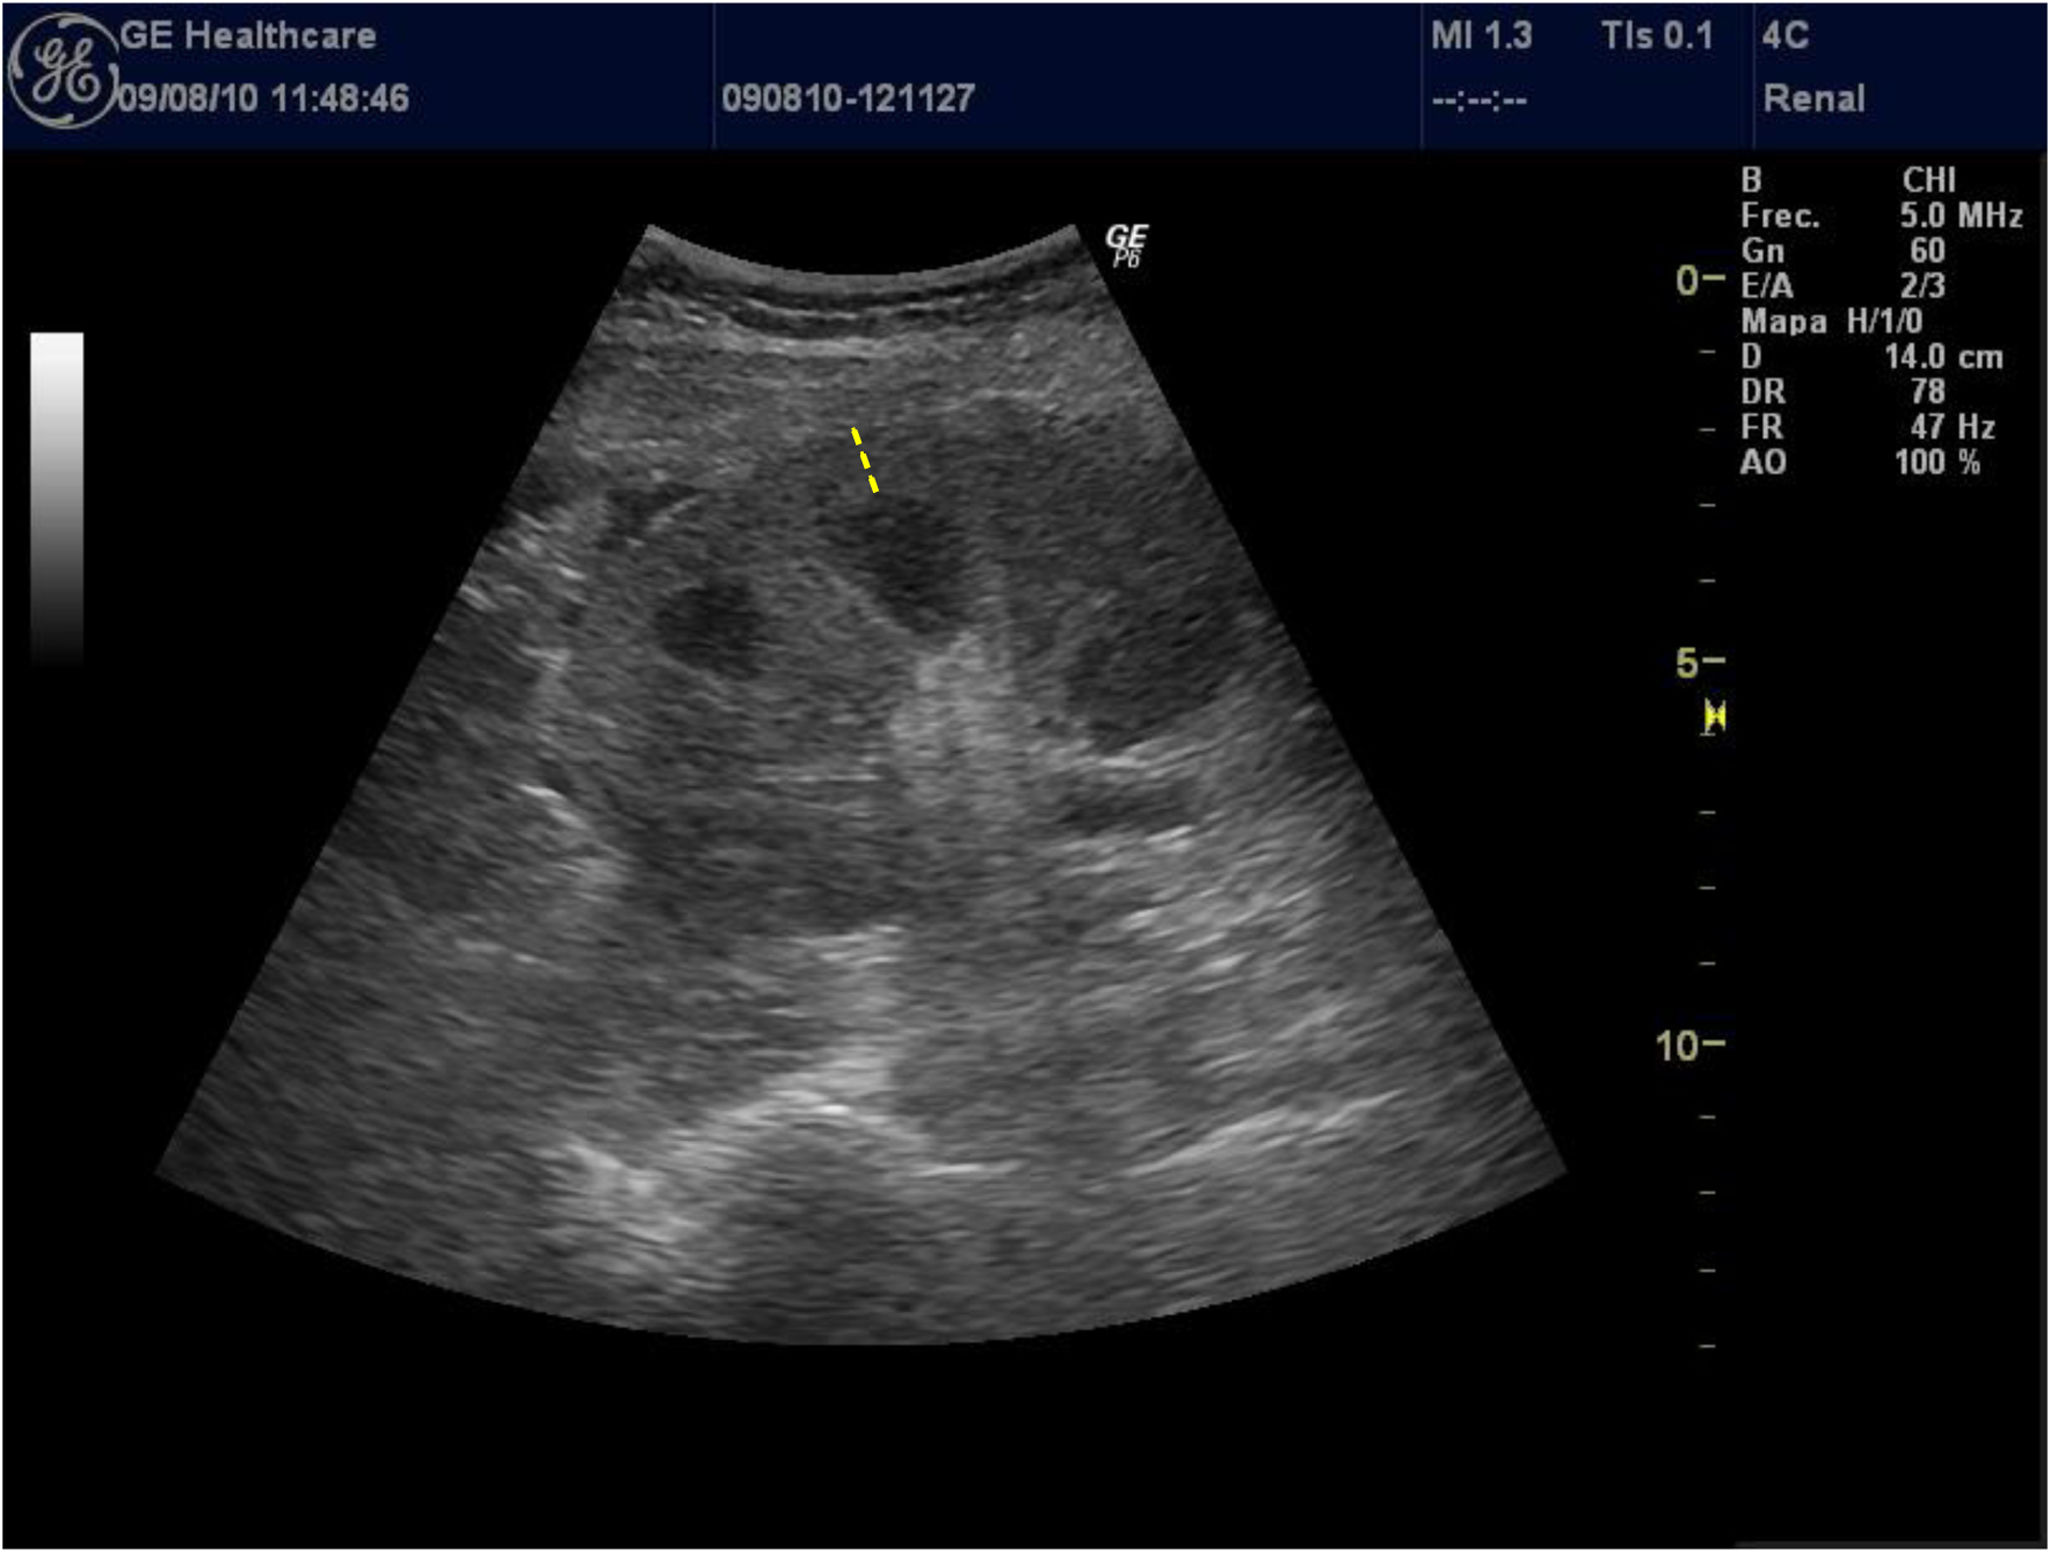

El parámetro del grosor de la corteza renal es poco utilizado por los investigadores por la dificultad de medición en pacientes con mala diferenciación coticomedular, hallazgo que se observa más frecuentemente en paciente con ERC avanzada. Al presentar una interfaz difícil de identificar, la reproductibilidad es baja, por este motivo pocos estudios lo utilizan y esto se traduce en que no haya datos consistentes acerca de la asociación de grosor de la corteza renal y deterioro de función renal. Asimismo, Beland et al.13 demostraron que el grosor de la cortical estaba estrechamente correlacionado con el FGe (fig. 2).

Por lo descrito anteriormente, los estudios encuentran que los parámetros que mejor se correlacionan con el FGe son la longitud renal y espesor parenquimatoso corregido por la altura corporal y peso1,12.